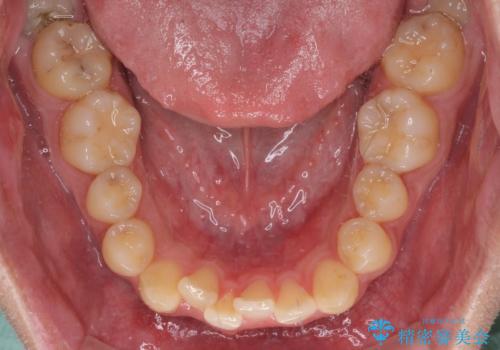

前歯のクロスバイト インビザラインによる矯正治療

- 上下のクロスバイトと前歯のデコボコを気にして来院された患者様です。

インビザラインを用い、IPR(歯と歯の間を削る)と歯列全体を拡大させることで、歯並びを整えていくこととしました。